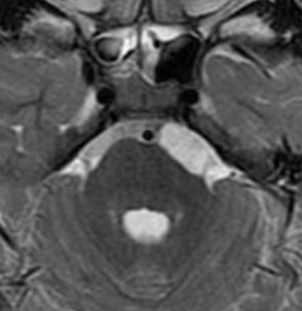

Проявления на МРТ схожи с таковыми на КТ; эпидермоиды часто неотличимы от арахноидальных кист или расширенных ликворных пространств на многих последовательностях.

- обычно неоднородный / "грязный" сигнал; выше, чем от ликвора

- остерегайтесь потоковых артефактов от пульсации ликвора, которые могут имитировать подобные изменения

При МРТ головного мозга картина неспецифическая и зависит от содержимого кисты. Если она не содержит жира, топри МРТ головного мозга эпидермоидная киста имеет ликворную интенсивность сигнала. В таком случае эпидермоидная киста трудно отличима от арахноидальной, хотя, как правило, не столь однородная. На FLAIR томограммах и диффузионно-взвешенных МРТ головного мозга содержимое эпидермоидов светлее ликворного. Жировое содержимое, такие эпидермоиды еще называют холестеатомой, приводит к высокому сигналу на Т1-зависимых МРТ головного мозга. Видимо, он обусловлен липидами, но не холестеролом. На Т2-взвешенных МРТ головного мозга он менее интенсивен чем ликвор. Контуры эпидермоидов на МРТ всегда четкие. Холестеатомы составляют всего 3-5% от эпидермоидов. В 15-20% случаев встречается кальцификация по переферии кисты. Редко наблюдается усиление стенок кисты при МРТ головного мозга с контрастированием.

МРТ головного мозга. Т2-взвешенная аксиальная МРТ. Эпидермоидная киста в области предмостовой цистерны слева.